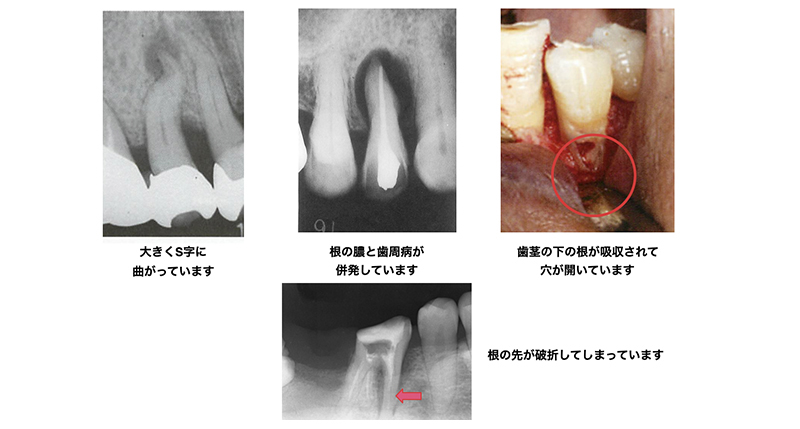

根管治療が困難なケース

- 器具の到達が困難な場合:(根が曲がっている 、根管が細くなっている 、根管が内部で枝分かれしている など)

- むし歯が深くまで進行している場合

- 歯根が病的な吸収を起こしている場合

- 歯周病を併発している場合

- 根が割れている・ヒビが入っている場合